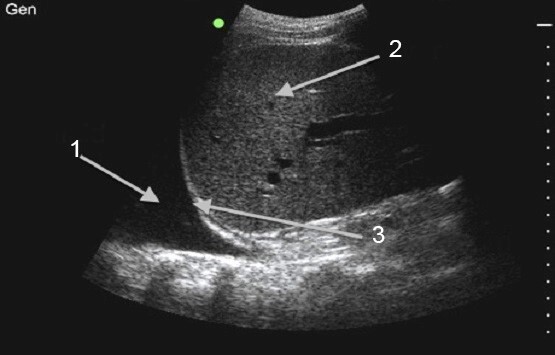

1. The lung is seen as an echogenic structure moving with respiration

2. Identify the most inferior fluid pocket while avoiding the lung, solid organ, and diaphragm

3. Measure to determine appropriate needle depth